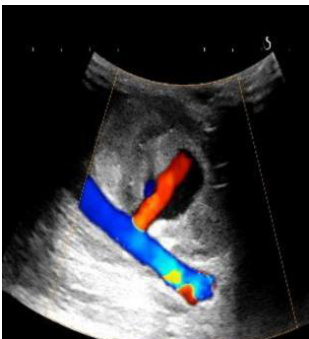

① 左上肢血管彩超:肱动脉近心段走行笔直血流充盈良好,流速 49-163cn/s,RI0.67,近肘段走行弯曲,于肱动脉近肘段前方可见一类囊实性结构,范围约 6.7cm×3.5cm. ,形态欠规则,边界大部分清晰,其类囊性回声范围约4.3cnx2.6cn,CDFI类囊性回声部可见红蓝血流信号,并可见一花色血流束与肱动脉相通,束宽约 0.44cm ,花色血流束处可测得往返血流频谱,入囊流速 300cm/s ,出囊流速 116cm/s。

图 1.肱动脉旁假性动脉瘤 彩色多普勒超声可见动脉壁缺损处朝向瘤体的高速喷射血流